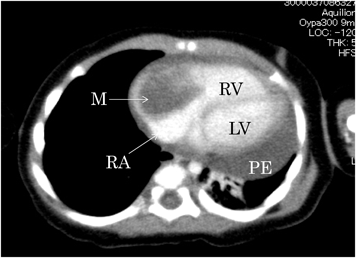

胸部エックス線撮影では心胸郭比67%と著明な心拡大を認めた.12誘導心電図は同調律,不完全右脚ブロックとIII誘導で異常Q波認めた.心エコー検査の傍胸骨短軸像と長軸像(Fig. 1)では,全周性に約15 mm心嚢水があり,左室拡張末期経(LVDd)=17.4 mm(z=-0.9)左室収縮率(LVFS)29%であった.四腔断面像では右房内に26×33 mmの内部不均一の腫瘤を認めた.腫瘤は右房壁に広範囲に接していて可動性はなく,右房内側の腫瘤表面は平滑であった.造影CTでは右房内に径27 mmの低吸収値の腫瘤を認めた(Fig. 2).血液検査では白血球数33,100/µL,CRP 10.3 mg/dL,血清アミロイドA 224 mg/mLと炎症反応の上昇を認め,IL-6 107.9 pg/mL,BNP 210.4 pg/mLと高値であった(Table 1).

Fig. 1 Transthoracic echocardiogram

(A) Short axis view showing pericardial effusion (white arrow). Left ventricular end-diastolic diameter (LVDd)=17.4 mm (z=−0.9). Left ventricular fractional shortening (LVFS)=29%. (B) Four-chamber view showing a mass of the internal heterogeneity of 26×33 mm in RA (white arrow).